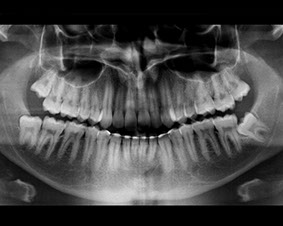

Durante la visita vengono esaminati i denti, la relazione tra le due arcate, l'articolazione temporo-mandibolare, la forma e il profilo del viso, il modo di chiudere i denti e di deglutire e, se necessario, si consiglia l'esecuzione di alcuni accertamenti diagnostici:

una radiografia delle arcate dentarie (che serve per verificare la presenza e la posizione dei denti decidui e permanenti)

una teleradiografia laterale (che serve per eseguire le misurazioni cefalometriche utili alla formulazione di un piano di trattamento ortodontico)

Le radiografie vengono eseguite con strumenti digitali di ultima generazione che servono per sottoporre il giovane paziente alla minor dose radiogena oggi possibile.